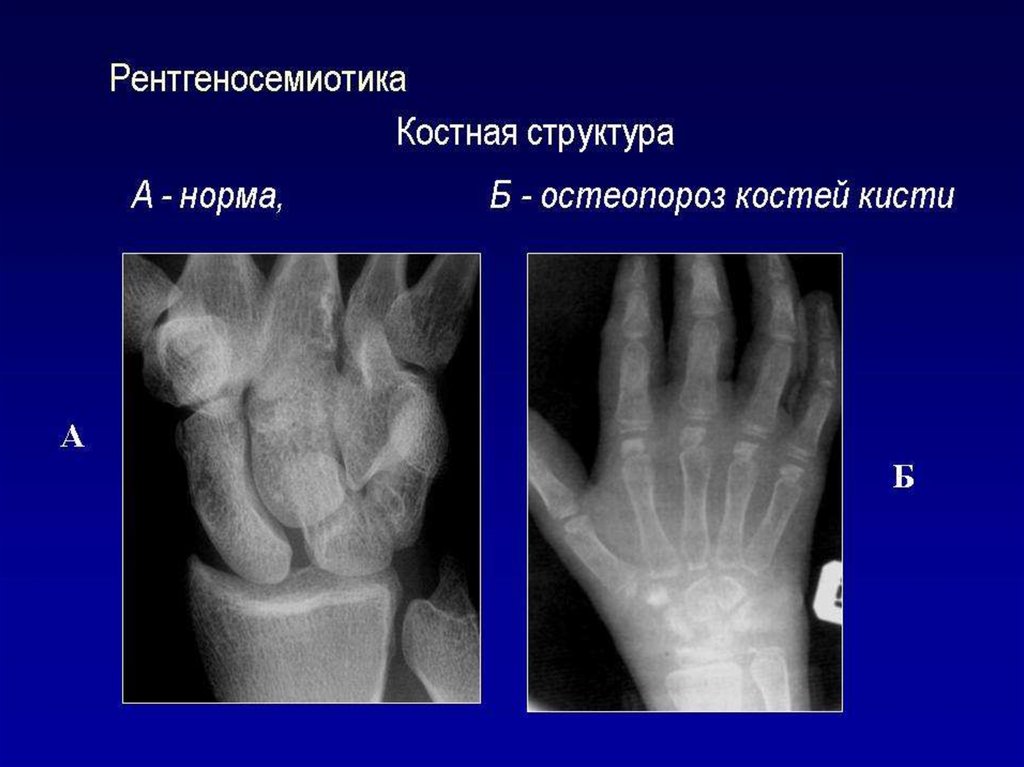

Лучевое исследование костно-суставной системы. Методы исследования. Семиотика